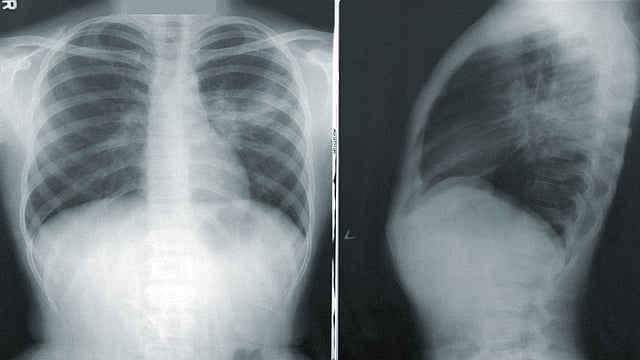

मुंबई - कोरोना संसर्गाचा वाढता प्रादुर्भाव पाहता जगभरातून कोरोनावर कसं नियंत्रण मिळवता येईल याबद्दल अनेक संशोधनं केली जातायत. यामध्ये कोरोनावर लस तर शोधली जातेच आहे. सोबतच कोरोनाची लक्षणं काय, कोरोना संक्रमण असेल तर ते किती आहे, त्याला लवकरात लावलात कसं शोधून काढता येईल यावर देखील अभ्यास सुरु आहे. याच पार्श्वभूमीवर IIT गांधीनगरमधील संशोधकांनी एक उपकरण बनवलंय. या उपकरणाद्वारा एखाद्या व्यक्तीला कोरोनाचं किती संक्रमण झालंय हे समजू शकणार आहे. एक्स रे प्रणालीवरील या उपकरणात आर्टिफिशियल इंटेलिजन्सवरचा आधार घेण्यात आलाय.

एखाद्या कोरोना संशयित रुग्णाच्या वैद्यकीय चिकित्सेआधी किंवा सोप्या भाषेत सांगायचं तर कोविड टेस्ट आधी हे उपकरण वापरलं जाऊ शकतं. इंडियन इन्स्टिट्यूट ऑफ पब्लिक हेल्थ IIPH द्वारा या आर्टिफिशियल इंटेलिजन्सवर आधारित उपकरणाचं परीक्षण आणि चाचणी केली जातेय.

कुशपाल सिंह यादव यांनी याबाबत माहिती दिलीये. ते IIT गांधीनगर मधील कॉम्प्युटर सायन्स आणि इंजिनिअरिंग विभागातील एम टेकचे विद्यार्थी आहेत. कोविड परीक्षण करण्यासाठी असलेली संसाधनं अत्यंत सीमित आहेत. याच पार्श्वभूमीवर एक्स रे प्रणाली आणि त्यातही आर्टिफिशियल इंटेलिजन्सवर आधारित हे उपकरण बनवण्यावर भर दिला जात असल्याचं ते म्हणतायत.

कुशापाल सिंह यादव यांच्या माहितीप्रमाणे ते ज्या मॉडेलवर काम करत आहेत त्यात टेक्निकल नेटवर्कचे १२ लेयर्स आहेत. हे लेयर्स माणसाच्या मेंदूतील न्यूरॉन सारखे काम करतात. या प्रोसेसमध्ये एक्स रे फोटोजच्या माध्यमातून कोरोना संसर्गाची माहिती मिळू शकते. अमेरिकेतील प्रिन्स्टन युनिव्हर्सिटीमध्ये देखील काही संशोधक आर्टिफिशियल इंटेलिजन्सवर आधारित उपकरण बनावट असल्याची माहिती आहे.